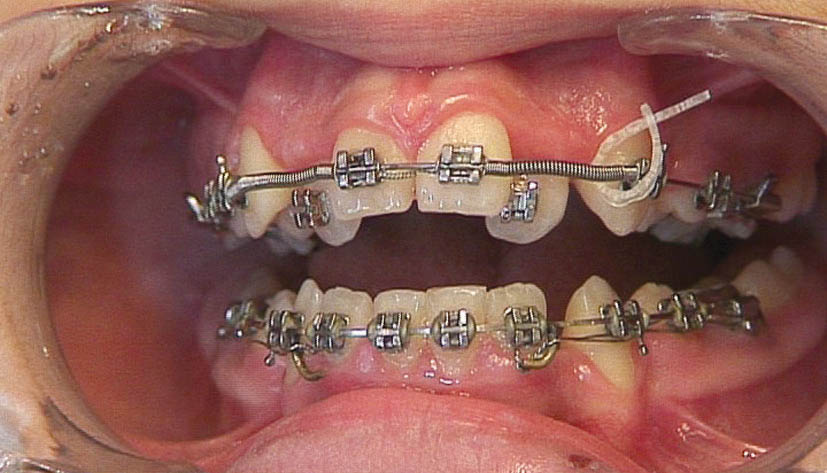

در بیماران به روش کشیدنی با استفاده از laceback دندان كانین را به دیستال حركت میدهیم تا فضا برای لترال پالاتالی فراهم شود. حركت دیستالی كانین باعث حركت مزیالی دندان 5 و 6 میشود. اگر حركت مزیالی دندان 6 مطلوب نباشد و هم چنین پروترود شدن سانترال نیز مد نظر باشد (اصلاح میدلاین یا اضافه کردن اورجت) به جای استفاده از laceback، از فنر استفاده میكنیم تا باعث جلو آمدن سانترال و عقب رفتن کانین به طور همزمان شود (شکل 185-1). به هنگام استفاده از فنر معمولاً

bendback نمیزنیم (خم کردن سیم در انتهای تیوب مولر دوم) تا فضا سریعتر باز شود.

با گذاشتن فنر باز بین براکتهای سانترال و کانین برای لترال فضا ایجاد میشود (شکل 185-1). برای این منظور مقداری از فنر open را (30 درصد بیشتر از فاصله دو براکت) بریده و آرچوایر را از درون آن رد میکنید. بعد از جا گذاری به علت فشرده شدن باعث اعمال نیرو شده و دو دندان سانترال و کانین را از هم دور میکند. اگر bendback زده باشید، فقط کانین عقب میرود اما اگر bendback نزده باشید هم کانین عقب میرود و هم سانترال جلو میآید. در صورتی که بین دو سانترال فضا باشد ابتدا فضا بسته میشود بعد سانترالها پروترود میشوند (و بدیهی است که اگر یکطرفه فنر گذاشته باشید مقداری میدلاین به سمت دیگر حرکت میکند).

شکل 185-1: بعد از مرتب شدن تمام دندانها به غیر از لترال، فنر باز بین براکت سانترال و کانین قرار میدهیم تا فضا برای لترال ایجاد شود.